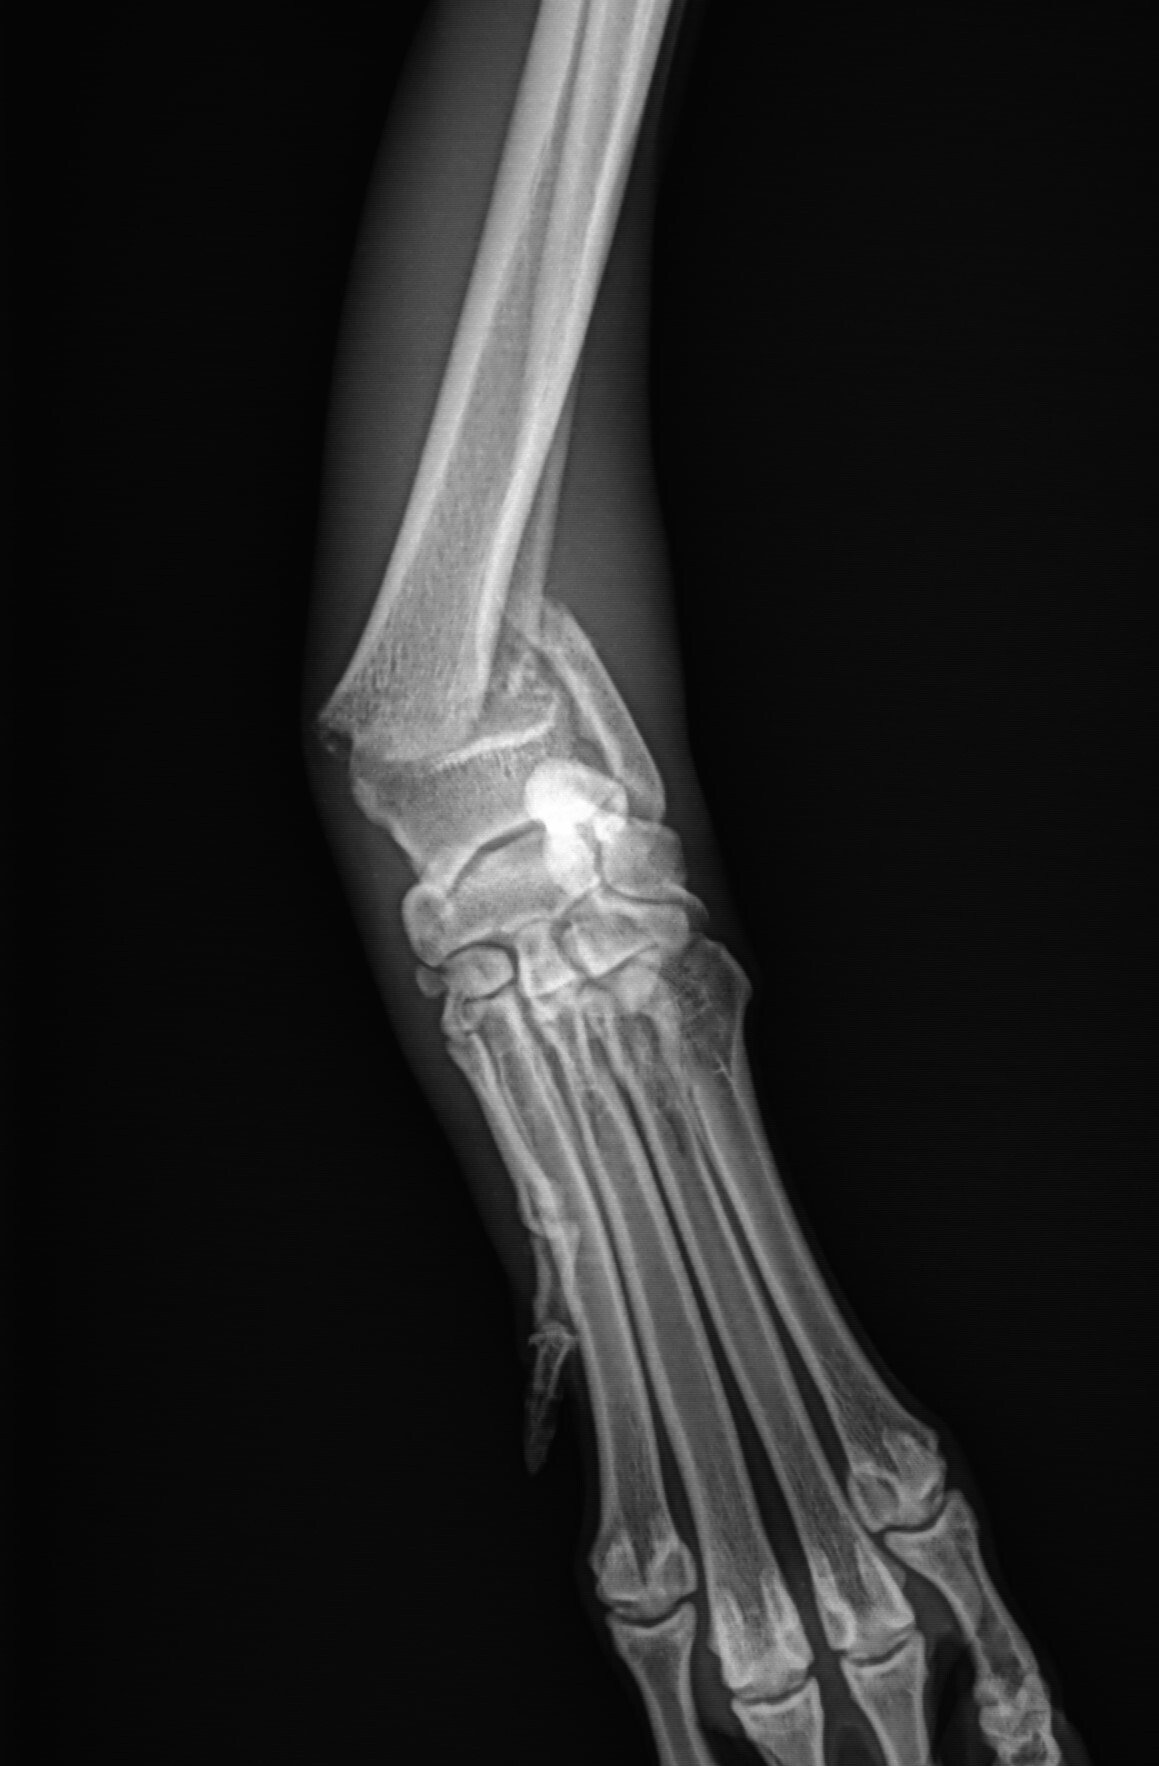

EMRad Radiologic Approach to the Pediatric Traumatic Elbow Xray Radius Bone Growth Plate  As a result, the blood supply to the area is compromised. The radius is on the thumb side of the forearm, and the ulna is on the pinky finger side.. Most growth plate fractures occur in the long bones of the fingers. The metaphysis is the broad region of bone right next to the physis. The diaphysis is the narrow. Radius Bone Growth Plate.

Kids Growth Plate Injury — Bone Talks Radius Bone Growth Plate  They are also common in the outer bone of the forearm (radius) and lower bones of the leg (tibia and fibula). Anatomic location of the growth plate fractures • fractures around the knee (proximal tibia & distal femur) have a much higher rate of growth. The epiphysis is the name given to the rounded end of a long bone also. Radius Bone Growth Plate.